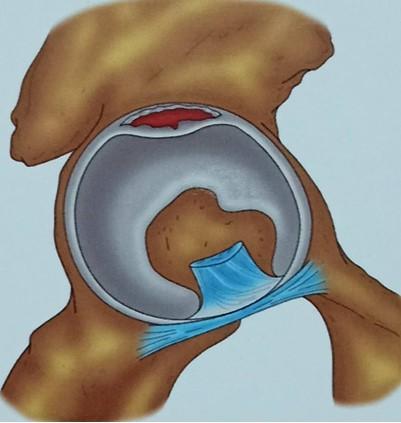

髋关节盂唇损伤必须做手术吗?不一定

髋关节盂唇损伤是一种常见的运动损伤,不仅影响运动员,也困扰着普通人群。然而, 并非所有盂唇损伤都需要手术治疗。 事实上,对于许多患者来说,保守治疗可能是一个更合适的选择。

髋关节盂唇损伤的治疗决策应该基于个体情况,由患者和医生共同决定。对于运动员或有高强度运动需求的人来说,可能需要更积极的治疗方案。而对于老年人或活动量较小的患者,保守治疗可能就足够了。